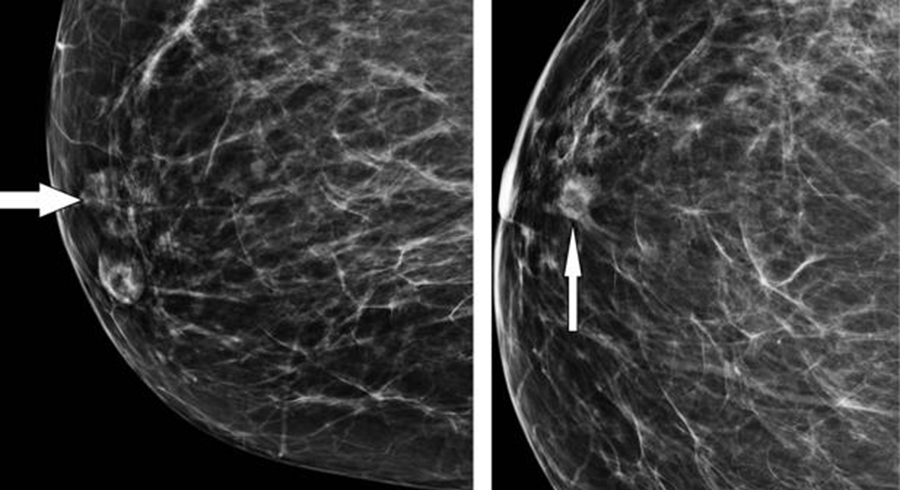

Toda esta acumulación de células que no son necesarias provoca la formación de una masa de tejido que se llama tumor, y que puede ser benigno o maligno. Para evitar el diagnóstico cuando ya es demasiado tarde, que es cuando las células cancerosas del seno viajan por los vasos sanguíneos o por el sistema linfático para llegar a otras partes del cuerpo, adherirse a otros tejidos y crecer para formar nuevos tumores (metástasis), hay que actuar de manera preventiva. La mamografía es el estudio aliado en esta tarea porque detecta signos radiográficos tempranos de cáncer, cuando aún no hay síntomas de la enfermedad. Es tan efectivo en esta misión que se ha comprado que reduce en casi un 30% el riesgo de mortalidad del cáncer de mama. La recomendación es que se realice de forma periódica desde los 40 años y si hay antecedentes de riesgo en la familia se debe hacer la mamografía a los 35 años, y si es normal, repetirla a partir de los 40 años anualmente.